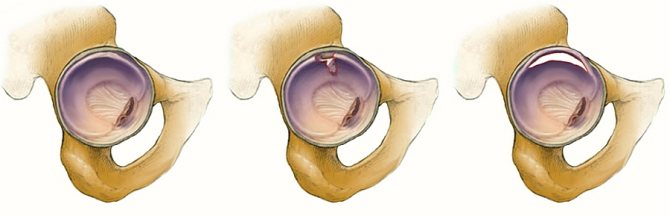

Разрыв губы вертлужной впадины

В связи с сильным ушибом или падением может разорваться вертлужная губа тазобедренного сустава, т.е поражается хрящевой ободок, проходящий по краю вертлужной впадины за счет своей мягкой структуры. При этом может нарушиться непрерывность мышечных тканей, сухожилий, бедренных связок, что требует необходимой экстренной помощи.

Но, к сожалению, данную травму часто длительное время не распознают, поскольку еще не наступили сильные болезненные ощущения. Позднее кратковременные боли становятся интенсивнее, появляется хруст и щелчки в суставе.

Иногда пострадавшие принимают боли за растяжение сухожилий и занимаются самолечением. Однако травма опасна своими долговременными последствиями.

При соприкосновении разорванных частей мягкой ткани губы с хрящами сустава происходит их утончение, захватываются и повреждаются новые здоровые ткани, а симптоматика усиливается.

Симптомы разрыва проявляются:

Слева – губа в норме, в центре – лоскутный разрыв, справа – разрыв по краю

Подтверждают диагностику МРТ и рентгеном и с помощью теста Joseph McCarthy. Для этого пациент должен лежать на спине и фиксировать таз, сгибая ноги.

Затем травмированную ногу разгибают и ротируют бедро наружу, затем его ротируют внутрь. При разрыве губы произойдет болезненный щелчок, больной ощутит боль также при подъеме выпрямленной ноги, преодолевая сопротивление врача.

При большом разрыве вертлужной губы проводят артроскопию тазобедренного сустава. Оторванную губу удаляют, устраняя механическую причину боли, или пришивают оторванную часть, что свободно болтается в полости сустава. Изредка при обширном краевом отрыве вертлужной губы накладывают артроскопический шов.

Разрыв губы и наложение артроскопического шва